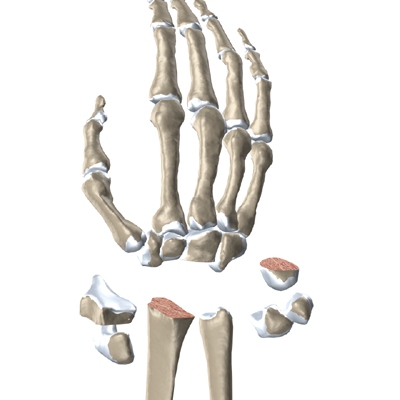

The wrist is made up of eight separate small bones, called the carpal bones. The carpal bones connect the two bones of the forearm, the radius and the ulna, to the bones of the hand. The metacarpal bones are the long bones that lie mostly underneath the palm. The metacarpals are in turn attached to the phalanges (the bones in the fingers and thumb).

One reason that the wrist is so complex is that every small bone forms a joint with the bone next to it. This means many small joints make up the wrist joint. Ligaments connect all the small bones to each other, and to the radius, ulna, and metacarpal bones.

The surgeon needs to make room for the artificial joint. To do this, most of the first row of:

Carpal Bones are Removed

from the wrist. The end of the radius is also shaped to fit the prosthesis.